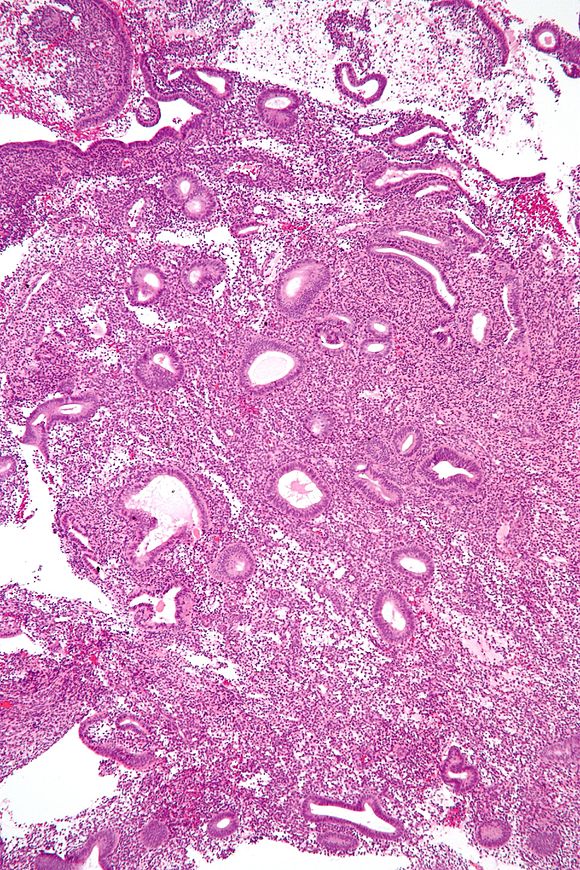

Endometrial hyperplasia is a condition characterized by the abnormal thickening of the uterine lining, also known as the endometrium. This relatively rare condition affects approximately 133 out of 100,000 women and can potentially lead to uterine cancer in some cases. To fully grasp the implications of this condition, it’s crucial to understand its underlying causes, symptoms, and available treatment options.

Endometrial hyperplasia occurs when the endometrium, the inner lining of the uterus, becomes excessively thick. This thickening is typically a result of hormonal imbalances, particularly an excess of estrogen without adequate progesterone to counterbalance it. During a normal menstrual cycle, the endometrium thickens in response to estrogen, preparing the uterus for potential pregnancy. If pregnancy doesn’t occur, the lining is shed during menstruation. However, in cases of endometrial hyperplasia, this normal cycle is disrupted, leading to an overgrowth of the uterine lining.

Endometrial hyperplasia is classified into two main types based on the cellular changes observed in the endometrium:

- Simple endometrial hyperplasia (without atypia): This type involves normal cells that are unlikely to be cancerous. In many cases, this condition may improve without treatment.

- Simple or complex atypical endometrial hyperplasia: This type is considered precancerous and results from an overgrowth of abnormal cells. If left untreated, it may progress to uterine or endometrial cancer.